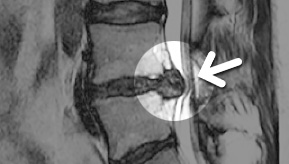

MRI

ϰ ڻ ͼ ̶ ؿ.

ü Ƶ ̰ ȣ µ

㸮 , ٸ ʹ

, Ƹ, ߰ ļ

ũ Ŀ

MRI ġ